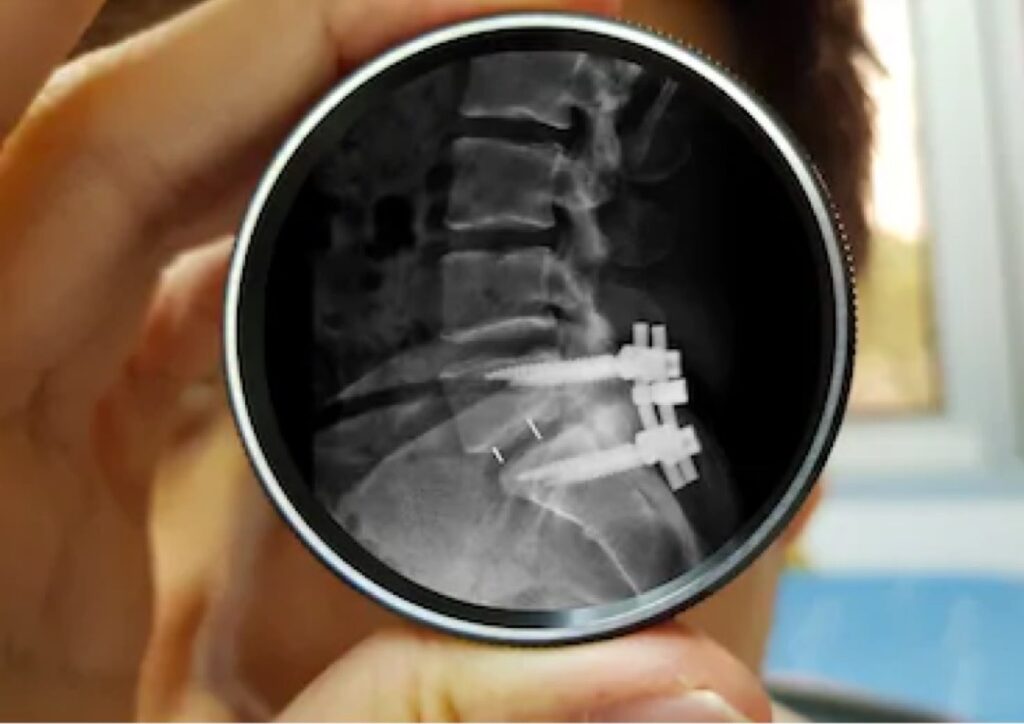

A diagnosis usually involves physical examination like checking health status, and imaging tests including X-ray, MRI or CT scan. They are useful in finding where stenosis is precisely and its extension. Based on that, doctors can treat the conditions with the following treatment.